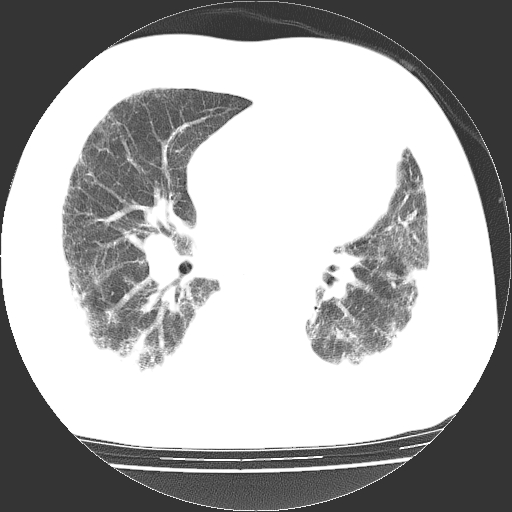

男,68岁,咳嗽、胸闷、发烧三天,查体:双肺散在湿罗音。

首先考虑特发型肺间质纤维化;两侧少量胸腔积液。

依据:1、两肺广泛条索状、网格状、蜂窝状改变。

1.双肺间质纤维化并感染;

2.双肺慢支炎肺气肿;

3.支扩并感染;

4.肺原性心脏病;

5.双侧胸腔少量积液;双侧胸膜增厚。

双肺多发条索状、网格状及小灶状密度增高影。考虑慢支合并感染.间质纤维化,双侧少量胸腔积液

两肺广泛条索状、网格状、蜂窝状改变。肺间质纤维化,肺心病,双侧胸腔积液